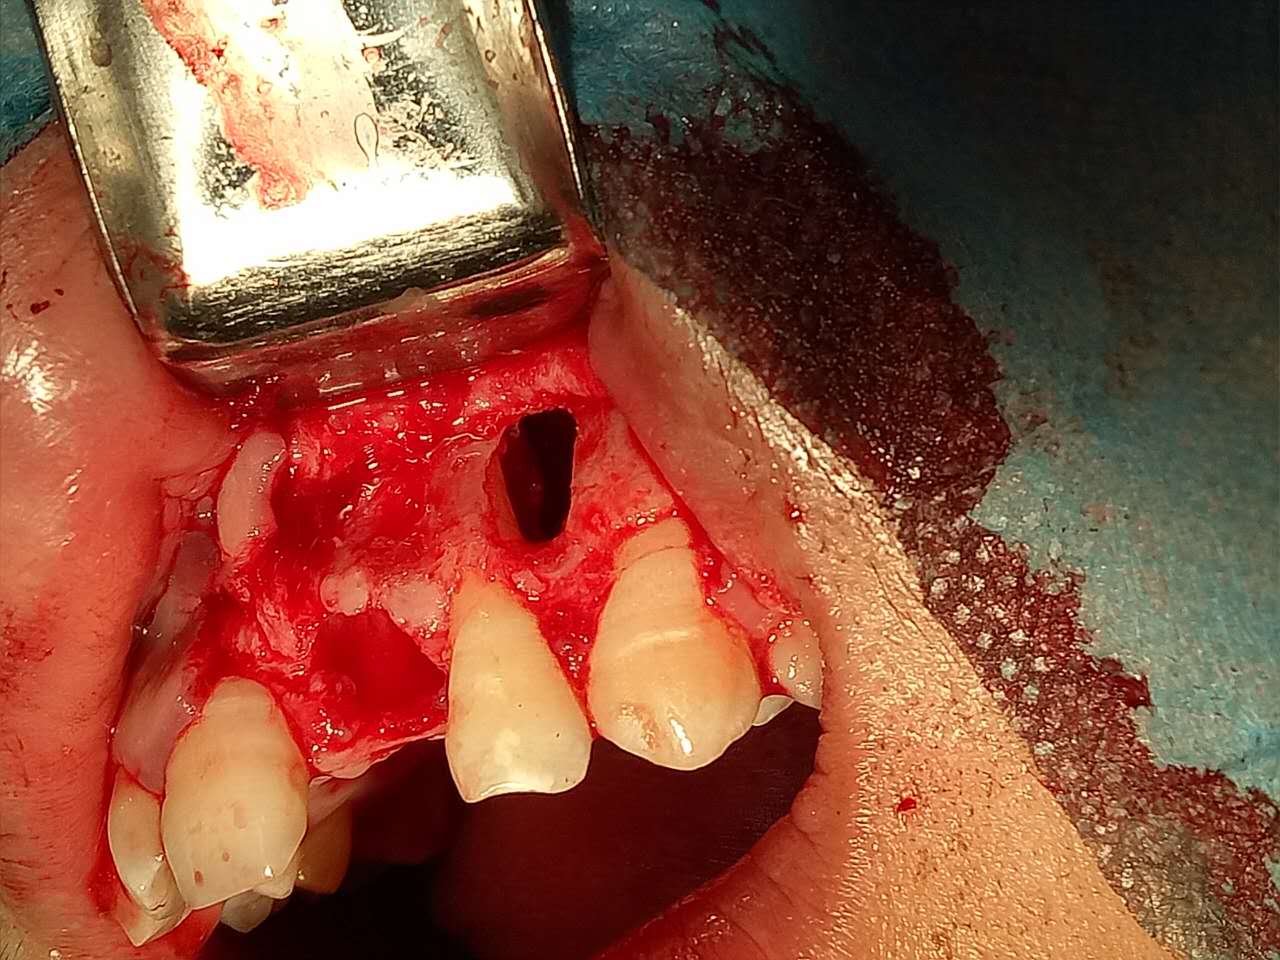

死髓牙2度,沒保留價(jià)值了,外傷造成的外吸收,即使到充也容易出問題。和患者溝通,要求做種植,用了兩個(gè)骨膠原,側(cè)切、尖牙沒事,側(cè)切做了一次根充